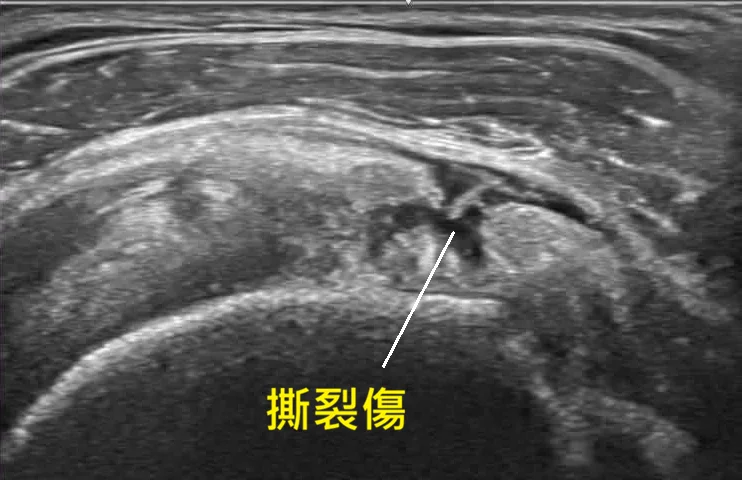

2. 超音波導引:差之毫釐,失之千里

注射位置不精準是失敗主因。我們堅持全程搭配高解析超音波導引,確保藥物精準打到患部撕裂處,這才是決定療效的最後一哩路。

💉 超音波導引:精準醫療的靈魂

在宸新復健科,我們堅持「眼見為憑」。醫師能將針頭精準引導至病灶核心,大幅提升治療成功率並減少疼痛。研究指出,超音波導引可確保 PRP 精準送達目標組織,是影響治療結果的關鍵因素[14]。